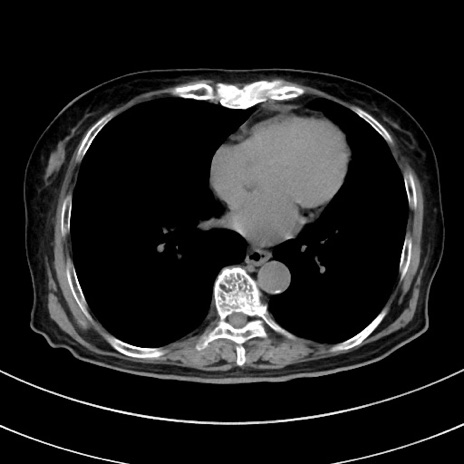

症例33(横断像)

【症例】70歳代 女性

【主訴】心窩部痛

【現病歴】延髄病変の精査・加療にて神経内科入院中。本日より心窩部痛あり。

【既往歴】虫垂炎

【身体所見】右下腹部を中心に圧痛と反跳痛あり。

【データ】WBC 10900、CRP 0.02